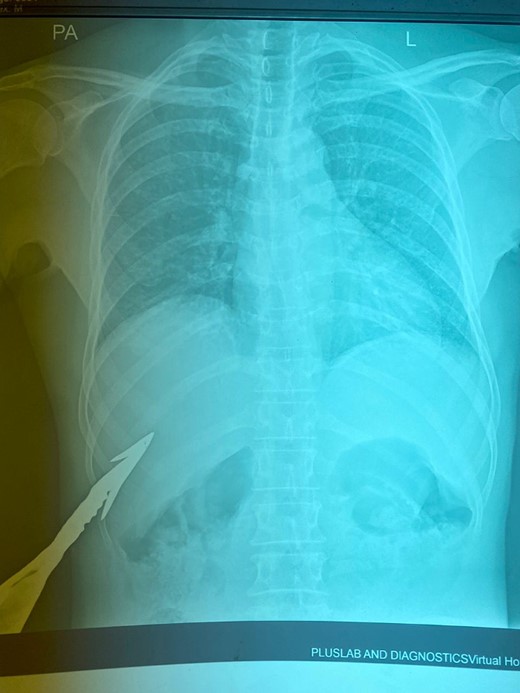

HB 9.9 mg/ml, sodium 135 mmol/L, chlorine 103 mmol/L, potassium 3.8 mmol/L, urea 4.3 mmol/L, and creatinine 108.5 umol/L. During the erect chest X-ray, the medical team observed the head of the spear within the abdominal cavity (Fig. 2), and a lateral chest X-ray confirmed its position in an ascending orientation (Fig. 3). The abdominal ultrasound showed the presence of a foreign body with an acoustic shade inside the liver parenchyma (Fig. 4); no free fluid was found in the Morrison’s pouch, but about 90 ml of free fluid was shown in the Douglass pouch. Both pleural spaces were free of fluid and had no pericardial fluid. We evaluated and discussed the possibility of performing an abdominopelvic computed tomography, but it was not feasible due to the patient's financial constraints.

Erect PA chest X-ray (impaled spear in the right hypochondrium).